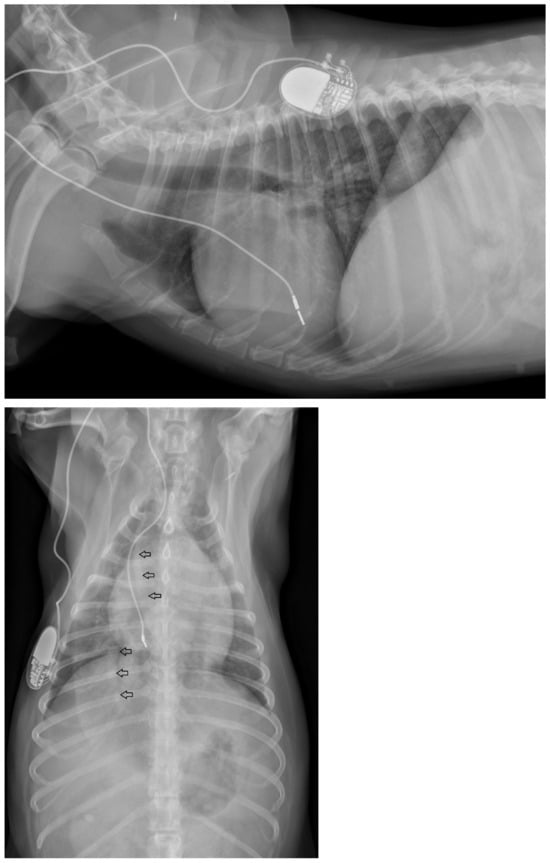

Physical examination at the authors’ institution, three years after the pacemaker implantation, revealed a bright, alert and responsive dog with a respiratory rate of 60 breaths/min and a pulse rate of 44 beats/min. The rectal temperature was 39.5 °C. The dog had received the last dose of antibiotics a day previously. Thoracic radiographs, an electrocardiogram, an echocardiogram, an abdominal ultrasound examination, urinalysis, and feces and blood tests were performed in order to identify the cause of the cough, hyperthermia and bradycardia. Thoracic radiographs showed no abnormalities and the position of the pacemaker lead was identical to that of the radiographs performed immediately after implantation (Figure 2). Electrocardiography showed a good functioning pacemaker, and ventricular premature complexes with periods of ventricular tachycardia (Figure 3 and Figure 4), which were assumed to have caused the pulse deficit.

Figure 2.

Thoracic radiographs of a dog with chronic cough, hyperthermia and increased respiratory rate show no pulmonary pathology and unchanged position of the pacemaker electrode compared to the direct post-operative radiographs.

At the next check-up a week later, the owner reported a gradual worsening of appetite and exercise tolerance, while frequent coughing remained unchanged. Every coughing episode was followed by gagging. In addition, the owner reported an increased respiratory rate at rest, frequent panting, and episodes of weakness during walks. Physical examination revealed a slightly depressed dog with an increased respiratory effort and a respiratory rate of 52 breaths/min. The femoral pulses were irregular with a rate of 60 beats/min. Rectal temperature was 38.6 °C. Thoracic radiographs were repeated, which showed a mild diffuse broncho-interstitial lung pattern, sternal lymphadenopathy and increased diameter of the lobar pulmonary arteries to the right cranial and right caudal lung lobes (Figure 6).

Figure 6.

Thoracic radiographs of a dog with chronic cough, hyperthermia and increased respiratory rate and effort show unchanged position of the pacemaker electrode compared to the direct post-operative radiographs. The open arrows indicate the prominent pulmonary artery branches to the right cranial and right caudal lung lobes.